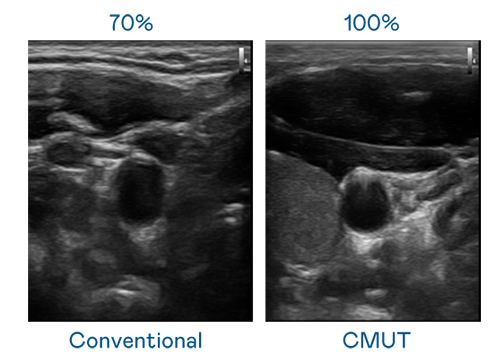

CMUT 技术是一种用电容式微机电元件来产生超音波讯号的技术。与传统 PZT 压电式技术相比,CMUT 频宽增加 30%,更宽频的超音波讯号让影像解析度大幅提升,是实现高影像品质医疗超音波扫描、促进精准医疗发展的关键技术。

大频宽带来超清晰影像

超音波影像的解析度高低,首先取决于探头能发出的讯号频宽。完美真人WM CMUT 可提供高清晰的超音波讯号,提供高频宽、高灵敏度、影像纹理细节更高的超音波影像,协助医护人员缩短影像判读时间及利用精准的医疗影像进行诊断。